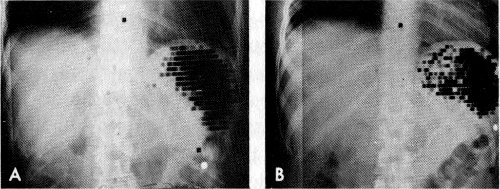

Spleen scans made with red blood cells, which had been altered by heat treatment and tagged with chromium-51. Such damaged cells are selectively removed by the spleen. A is a normal spleen. B shows an abscess in the spleen. Note dark ring of radioactivity surrounding the lighter area of decreased activity at the central portion of spleen.

In certain types of anemia the patient’s red blood cells die before completing the usual red-cell lifetime of about 120 days. To diagnose this, red cells are tagged with chromium-51 (⁵¹Cr) in the manner just described. Then 16 some of them are injected back into the patient and an identical sample is injected into a compatible normal individual. If the tracer shows that the cells’ survival time is too short in both recipients to the same degree, the conclusion is that the red cells themselves must be abnormal. On the other hand, if the cell-survival time is normal in the normal individual and too short in the patient, the diagnosis is that the patient’s blood contains some substance that destroys the red cells.